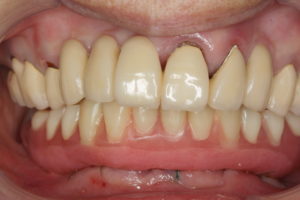

ですから、手術前は入れ歯だったのが、手術後にはまるで自分の歯のようなブリッジが出来上がり、食事ができるようになります。手術方法によってはほとんど腫れや痛みもありません。(今回は、余分な骨を削ったり、骨移植を行ったりしたため、翌日若干の痛みが出たそうです。)

手術当日に入れたブリッジは仮の歯なので、硬い物は控えて頂いていますが、3ヶ月後には最終的な物が出来上がり、なんでも食べられるようになります。入れ歯では食べられないような、アワビやタコのようなものも食べられるようになります。

ただし、嫌いな物は食べられるようになるとは限りませんが(以前治療後に「ずいぶんいろんなものが食べられるようになったけれど、嫌いな物だけは食べられるようにならないわ」とおっしゃっていた方がいらっしゃったもので・・・)。この症例の詳細は後日ご報告します。